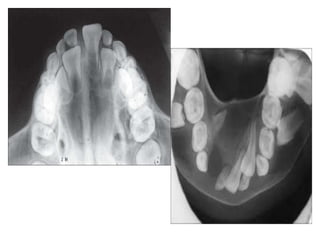

Occlusal radiographs

• These are used in the evaluation of the entire

maxillary and mandibular arch.

• A larger film is used to cover the larger area in

one film.

• When smaller No. 2 film is used, the procedure is

called “cracker bite” or “coolie” occlusal.

• It is not indicated in children as it does not press

the floor of mouth or tickle the soft palate.

Occlusal radiographs • Theseare used in the evaluation of the entire maxillary and mandibular arch. • A larger film is used to cover the larger area in one film. • When smaller No. 2 film is used, the procedure is called “cracker bite” or “coolie” occlusal. • It is not indicated in children as it does not press the floor of mouth or tickle the soft palate.